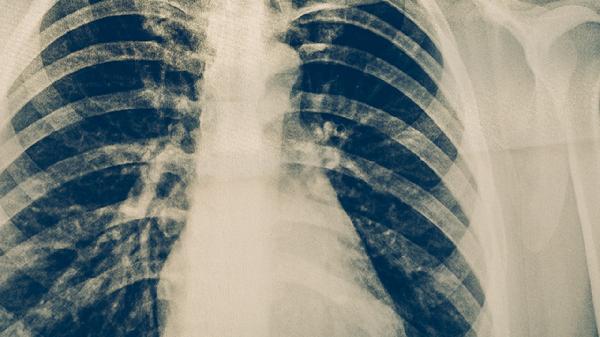

病理活检是诊断肺癌的金标准,通过获取病变组织进行病理学检查,可以明确肺癌的类型和分化程度。常用的活检方式包括经皮肺穿刺活检、支气管镜下活检和手术切除活检。影像学检查在肺癌诊断中具有重要作用,胸部X线可以发现肺部占位性病变,而胸部CT能够更清晰地显示肿瘤的大小、位置和周围组织关系。PET-CT检查有助于判断肺癌是否发生远处转移。